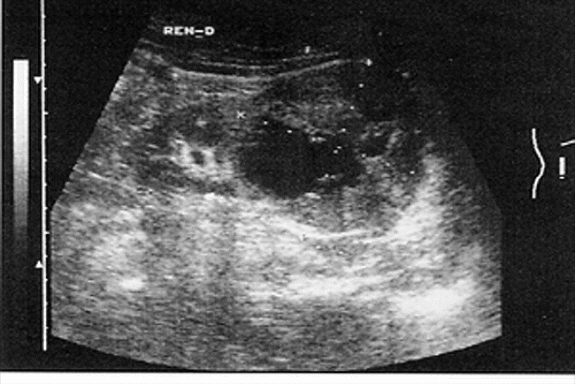

ПРОФЕССИОНАЛЬНАЯ ЗАДАЧА № 49

Больной 58 лет поступил в клинику с жалобами на общую слабость, плохой аппетит, длительный субфебрилитет, неоднократно выделение крови с мочой без болевых ощущений, за последние 6 месяцев похудел на 10 кг.

Объективно: Живот мягкий. Пальпируется объемное образование в левой поясничной области: гладкое, безболезненное, слабо подвижное. Отмечается расширение вен семенного канатика слева, которое появилось около 5 месяцев назад. Простата без особенностей. Мочеиспускание свободное, моча окрашена кровью, отходят сгустки в виде «червячков». На обзорной урограмме гомогенное затемнение в левой поясничной области. В OAK обращает на себя внимание эритремия.

1. Предположительный диагноз

а)опухоль левой почки

2. укажите наиболее простой метод, позволяющий уточнить диагноз

а)УЗИ почек

УЗИ левой почки